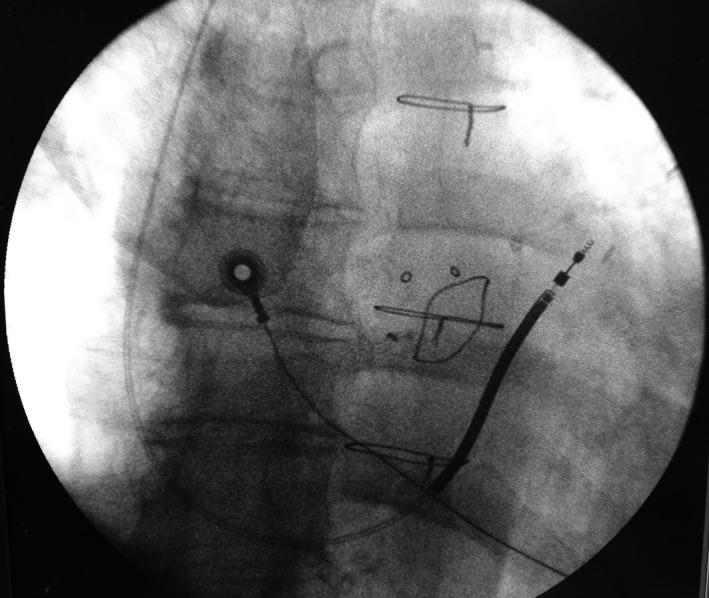

Inappropriate implantable cardioverter defibrillator shocks due to atrial far-field on the tip-to-ring channel for lead dislodgement.

We reported a case of inappropriate implantable cardioverter defibrillator shocks, due to atrial far-field on the tip-to-ring channel of the fast electrical activity during atrial fibrillation, caused by lead dislocation in the right ventricle outflow tract. During these episodes the can-to-right ventricle coil signal correctly recorded the ventricular activity. The shock storm stopped when an antitachycardia pacing restored sinus rhythm.

我们报告了一例不适当的植入式心脏复律除颤器电击事件,其原因是右心室流出道导线脱位导致房颤期间快速电活动的尖端至环通道出现心房远场信号。在这些发作期间,罐至右心室线圈信号正确记录了心室活动。当抗心动过速起搏恢复窦性心律时,电击风暴停止。